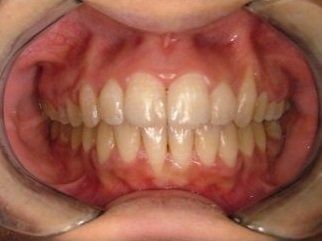

L’ortodonzia non dimentica neanche l’importanza dell’estetica e la sicurezza che un bel sorriso può portare. Per questo un apparecchio può avere come obiettivo anche quello di riportare il profilo facciale nella posizione più corretta possibile e di restituire al paziente un aspetto migliore, oltre che la fiducia in se stesso.

Quindi, in conclusione, un trattamento ortodontico ha i seguenti vantaggi:

- può migliorare l'aspetto e la funzione dei denti;

- la capacità di parlare e masticare può essere migliorata;

- denti più dritti facilitano lo spazzolamento e per questo sono meno soggetti a carie e altre patologie.